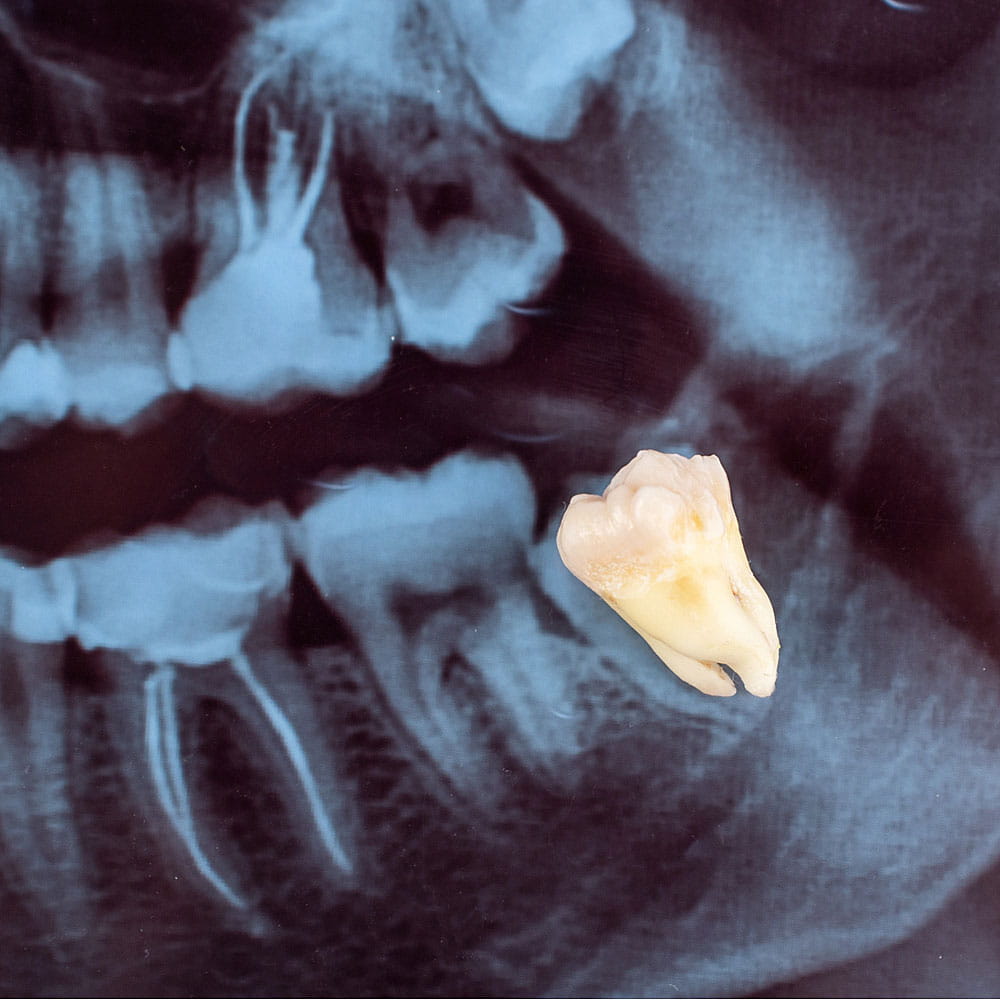

Among the comprehensive range of services we provide, tooth extraction is one that many people fear. It’s not just about removing a tooth; it’s about ensuring the overall health of the mouth. Whether it’s an impacted wisdom tooth causing discomfort or severe decay threatening the health of surrounding teeth, our team is equipped to handle it with precision and care.

Tooth extraction, often colloquially referred to as “pulling a tooth”, is the process of completely removing a tooth from its socket. While our team at Happy Smiles Dentist always aims to preserve natural teeth, there are instances when extraction becomes the most viable option for the patient’s overall oral health.